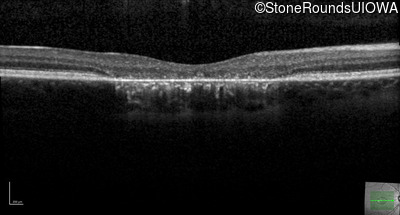

This 22 year old man had macular abnormalities noted incidentally at a routine eye exam at age 19. Since then, he has experienced a gradual loss of acuity particularly in the left eye.

| AR Stargardt Disease | ABCA4 | Tyr245Stop TAT>TAG | Unknown | AR |